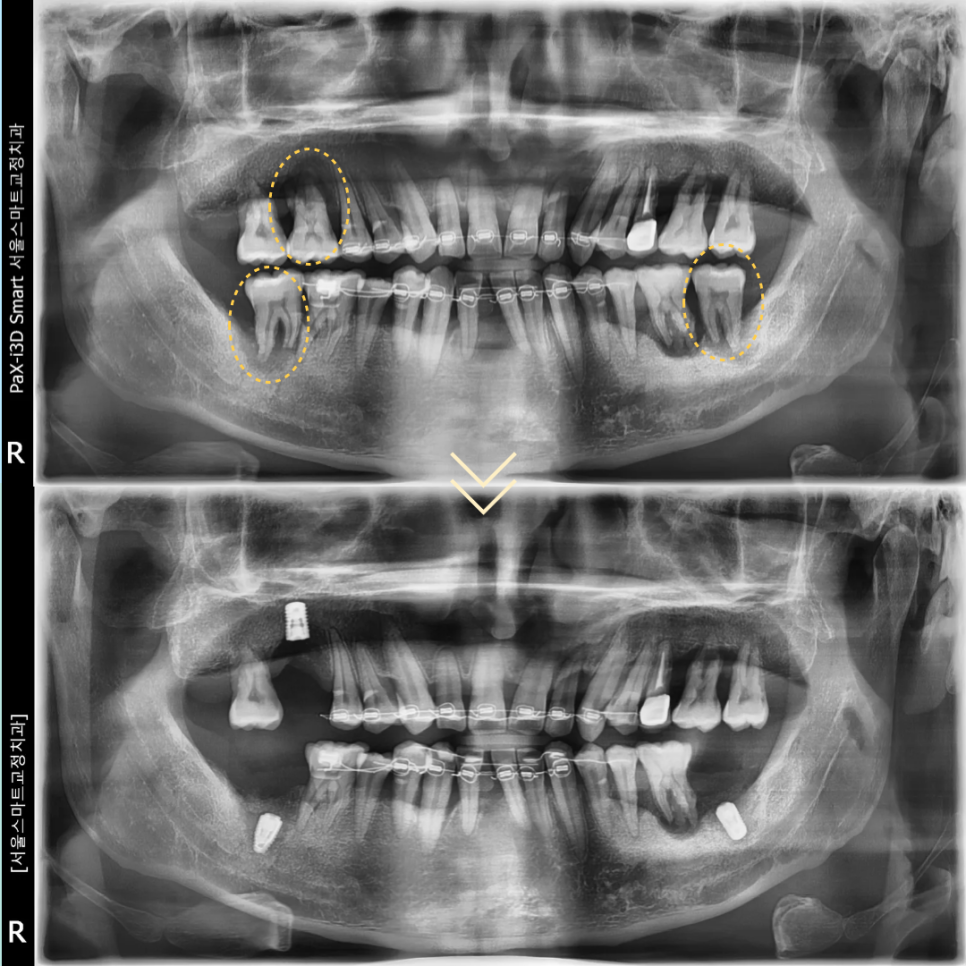

전치부의 배열을 진행하면서

치조골의 파괴가 심각한 어금니 3개를 발치하고

임플란트를 식립하였습니다.

우측 위아래는 최종보철을 완성하여

식사를 조금이라도 하실 수 있도록 진행하였으며

왼쪽 아래는 첫번째 큰 어금니 식립과 함께

보철을 연결하기위해서

현재 식립한 임플란트에는 임시치아를 제작하여

다음 과정 전까지 사용하기로 하였습니다.

앞니 교정을 마무리하면서

기존에 발치를 했던 아래의 앞니부분은

브릿지로 빠르게 수복 완료한 뒤

유지장치를 부착하였습니다.

동시에 왼쪽위의 어금니는 발치 후

치조골이식술을 동반하여

임플란트를 3개 식립하였습니다.